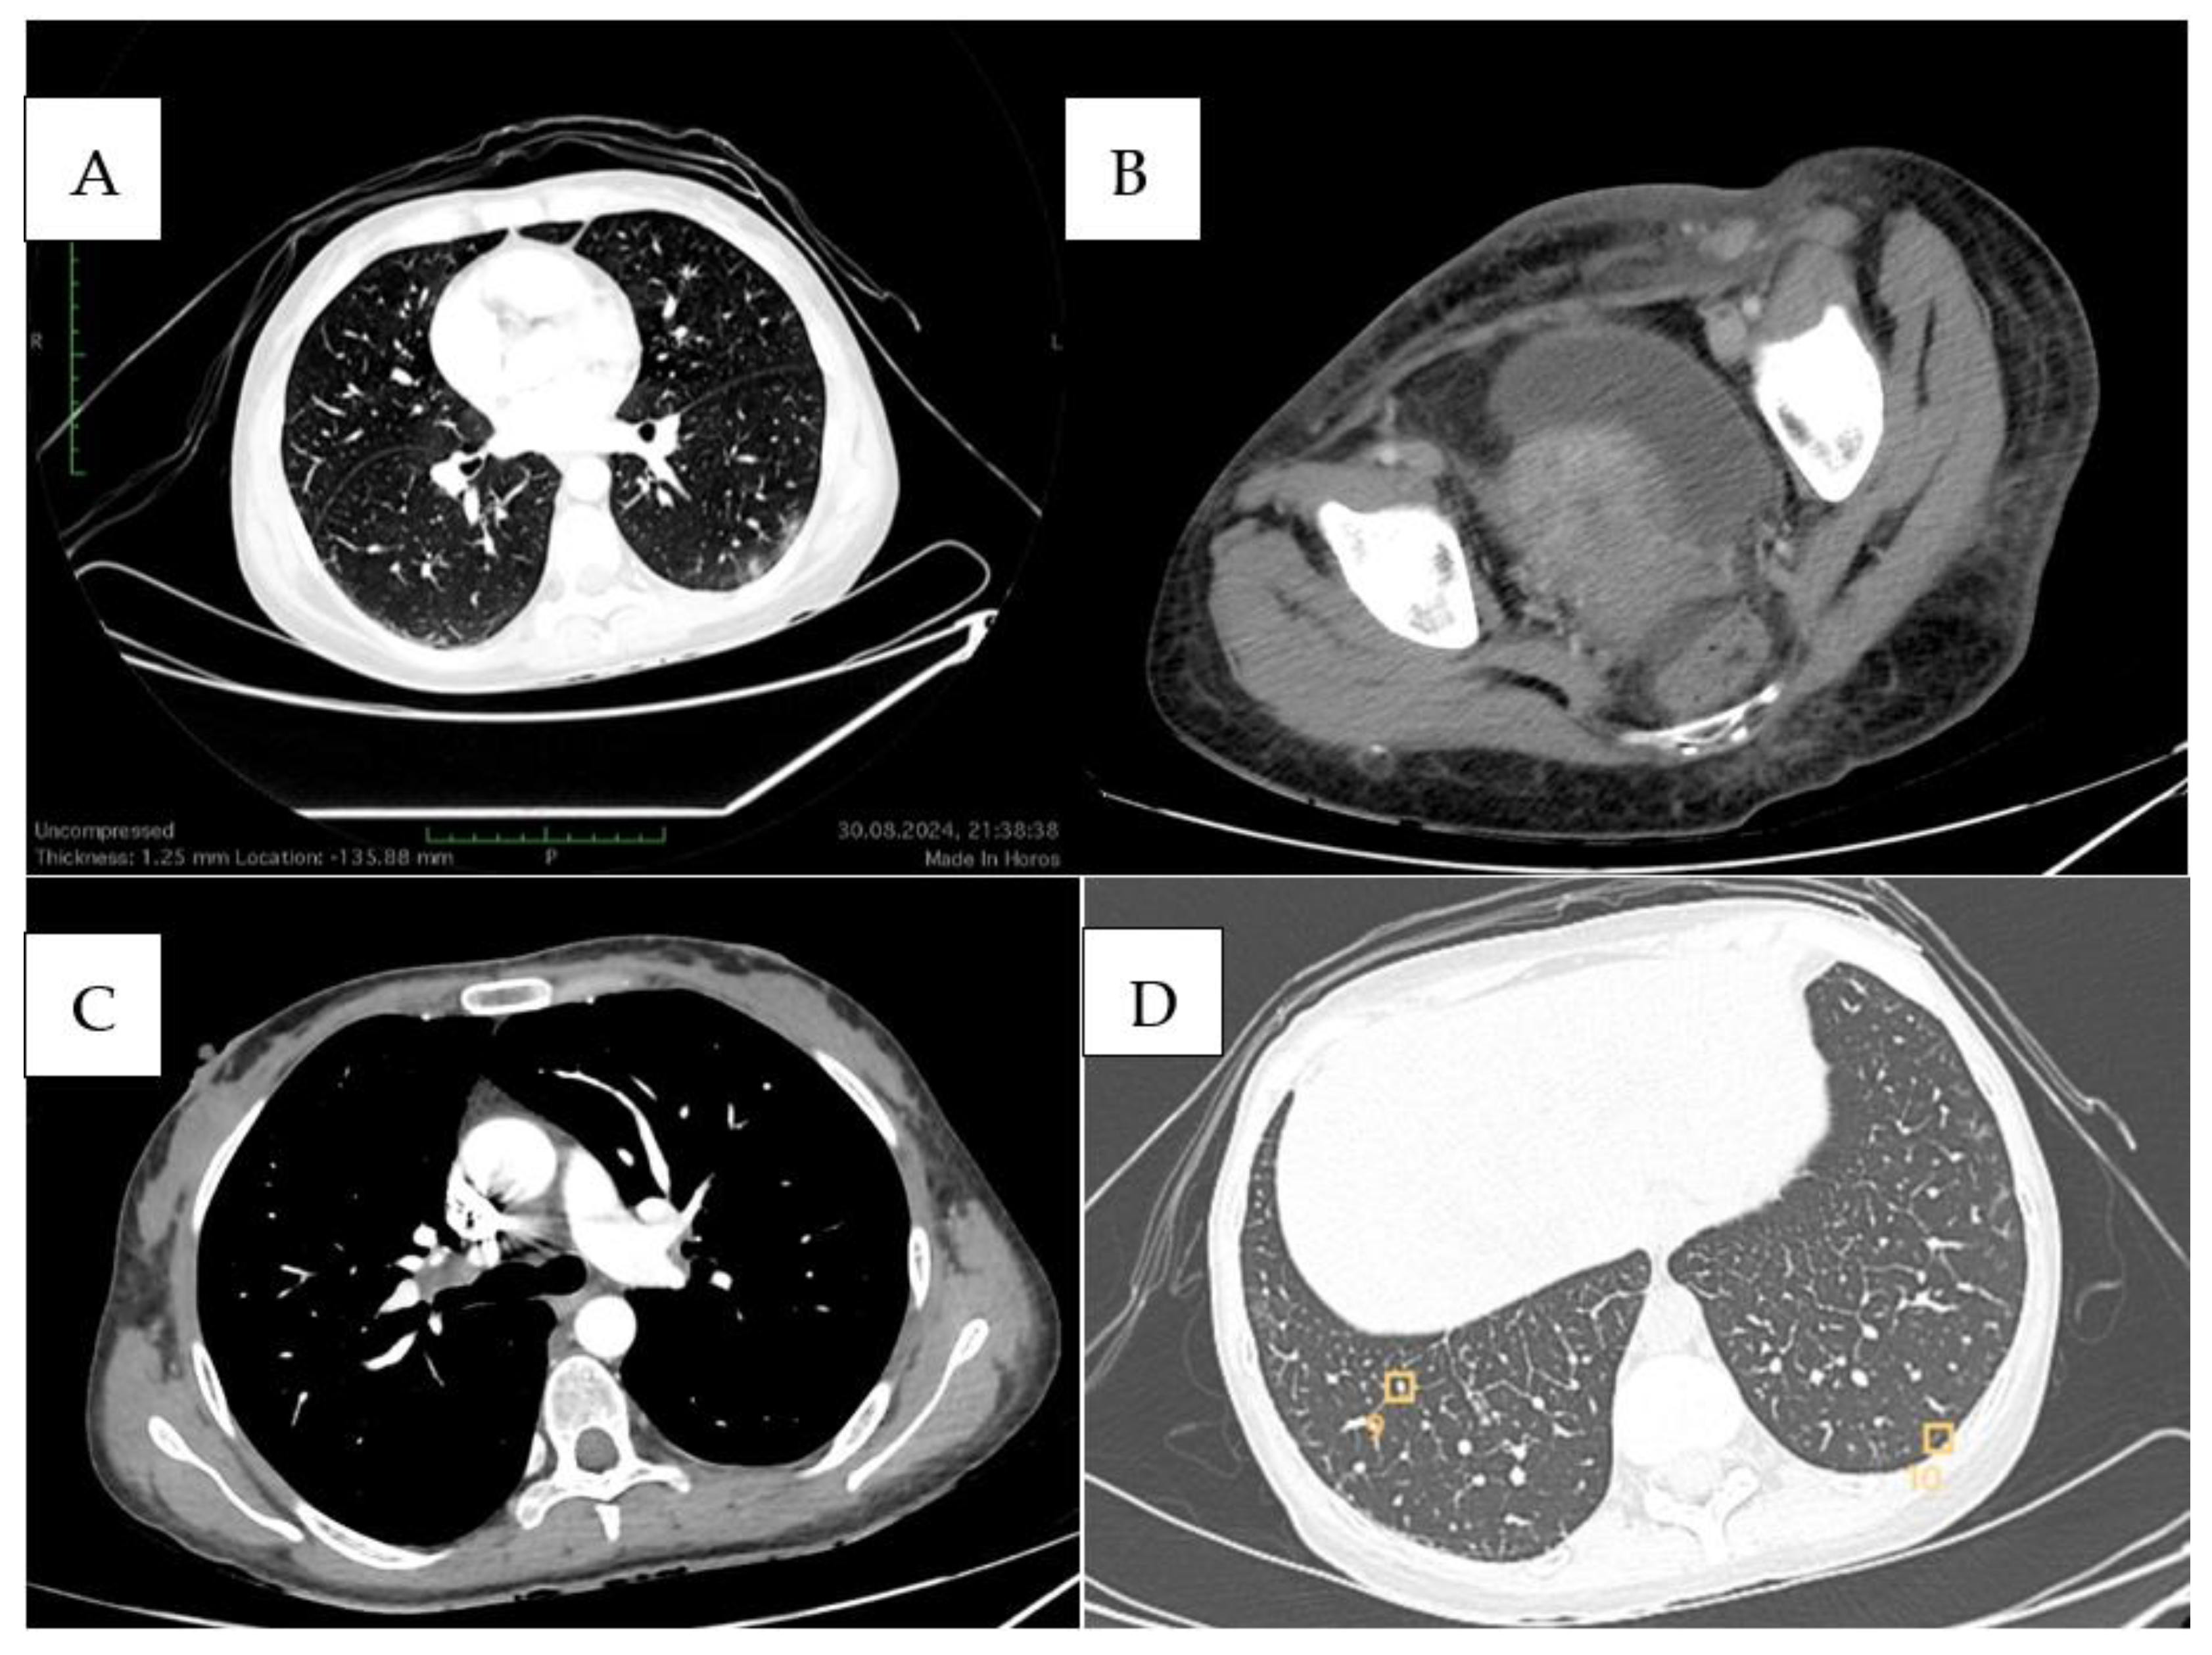

- Kim, J.S.; Jeong, Y.J.; Sohn, M.H.; Jeong, H.J.; Lim, S.T.; Kim, D.W.; Kwak, J.Y.; Yim, C.Y. Usefulness of F-18 FDG PET/CT in subcutaneous panniculitis-like T cell lymphoma: Disease extent and treatment response evaluation. Radiol. Oncol. 2012, 46, 279–283. [Google Scholar] [CrossRef] [PubMed] [PubMed Central]